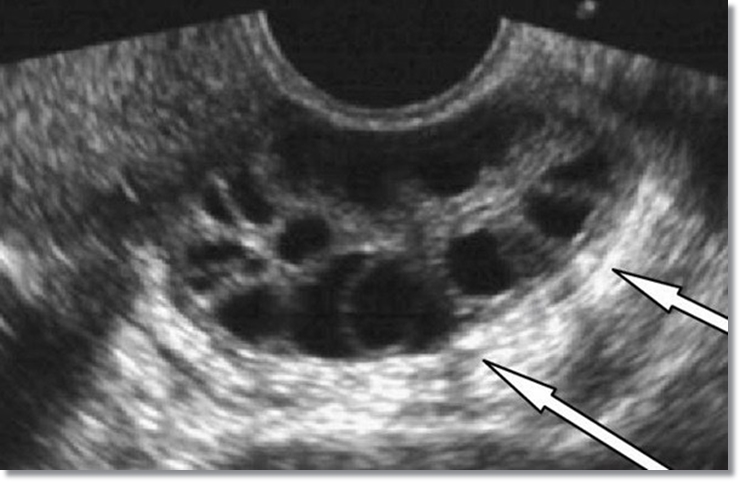

다낭성 난소증후군(PCOS)이란?

호르몬 불균형으로 인해 난소에 많은 작은 낭종이 생기면서 커진 난소와 여러가지 특별한 증상이 존재하는 증상입니다.